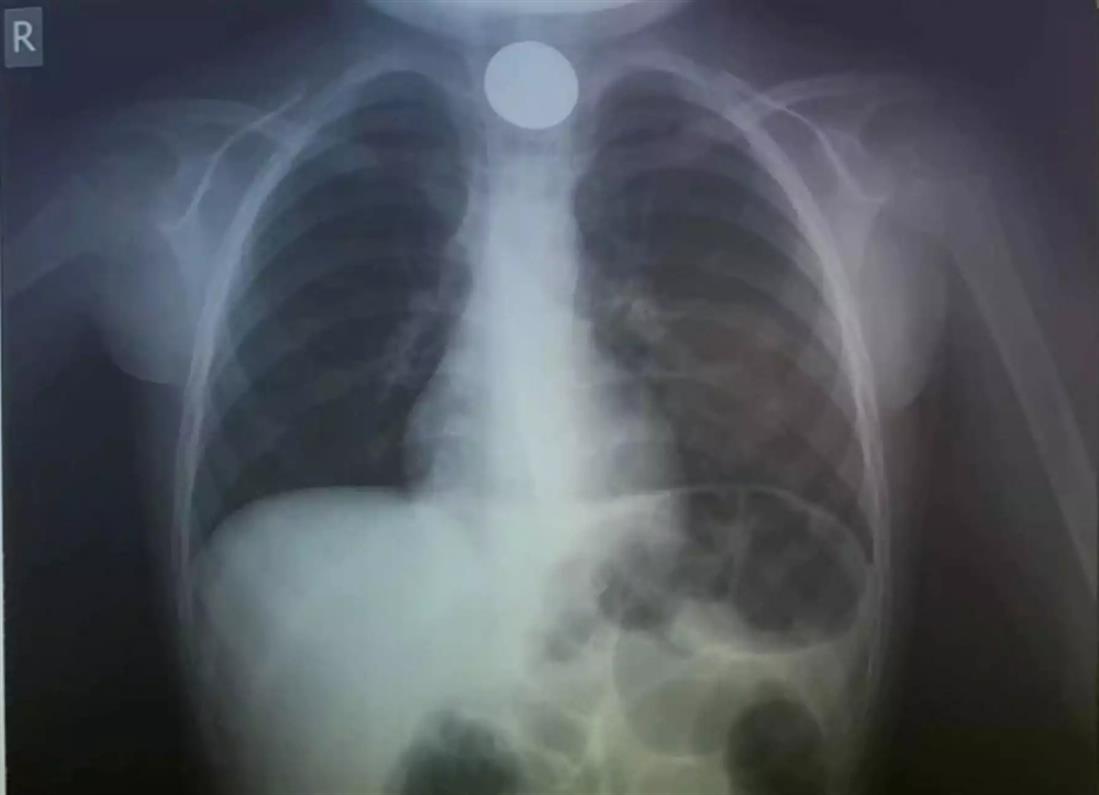

Η πρώτη κίνηση των γιατρών, ήταν να του κάνουν ακτινογραφία, για να δουν το σημείο που είχε σταθεί το νόμισμα.